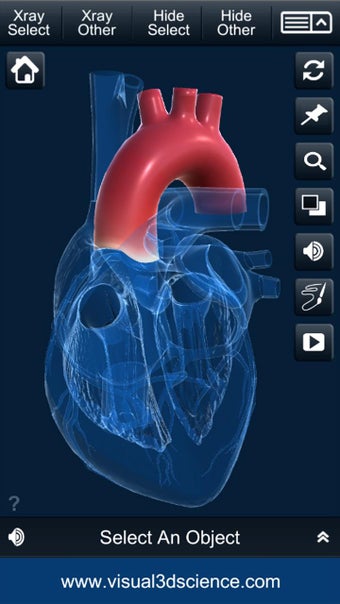

Es muy fácil de usar y muy interactiva. Puedes rotar 360°, hacer zoom y mover la cámara alrededor de un modelo 3D altamente realista.

Puedes seleccionar la vista de rayos X, ocultar y mostrar partes del corazón, así como ver animaciones en tiempo real, dibujar o escribir en la pantalla y compartir capturas de pantalla, pronunciación de audio para todos los términos de anatomía y más.